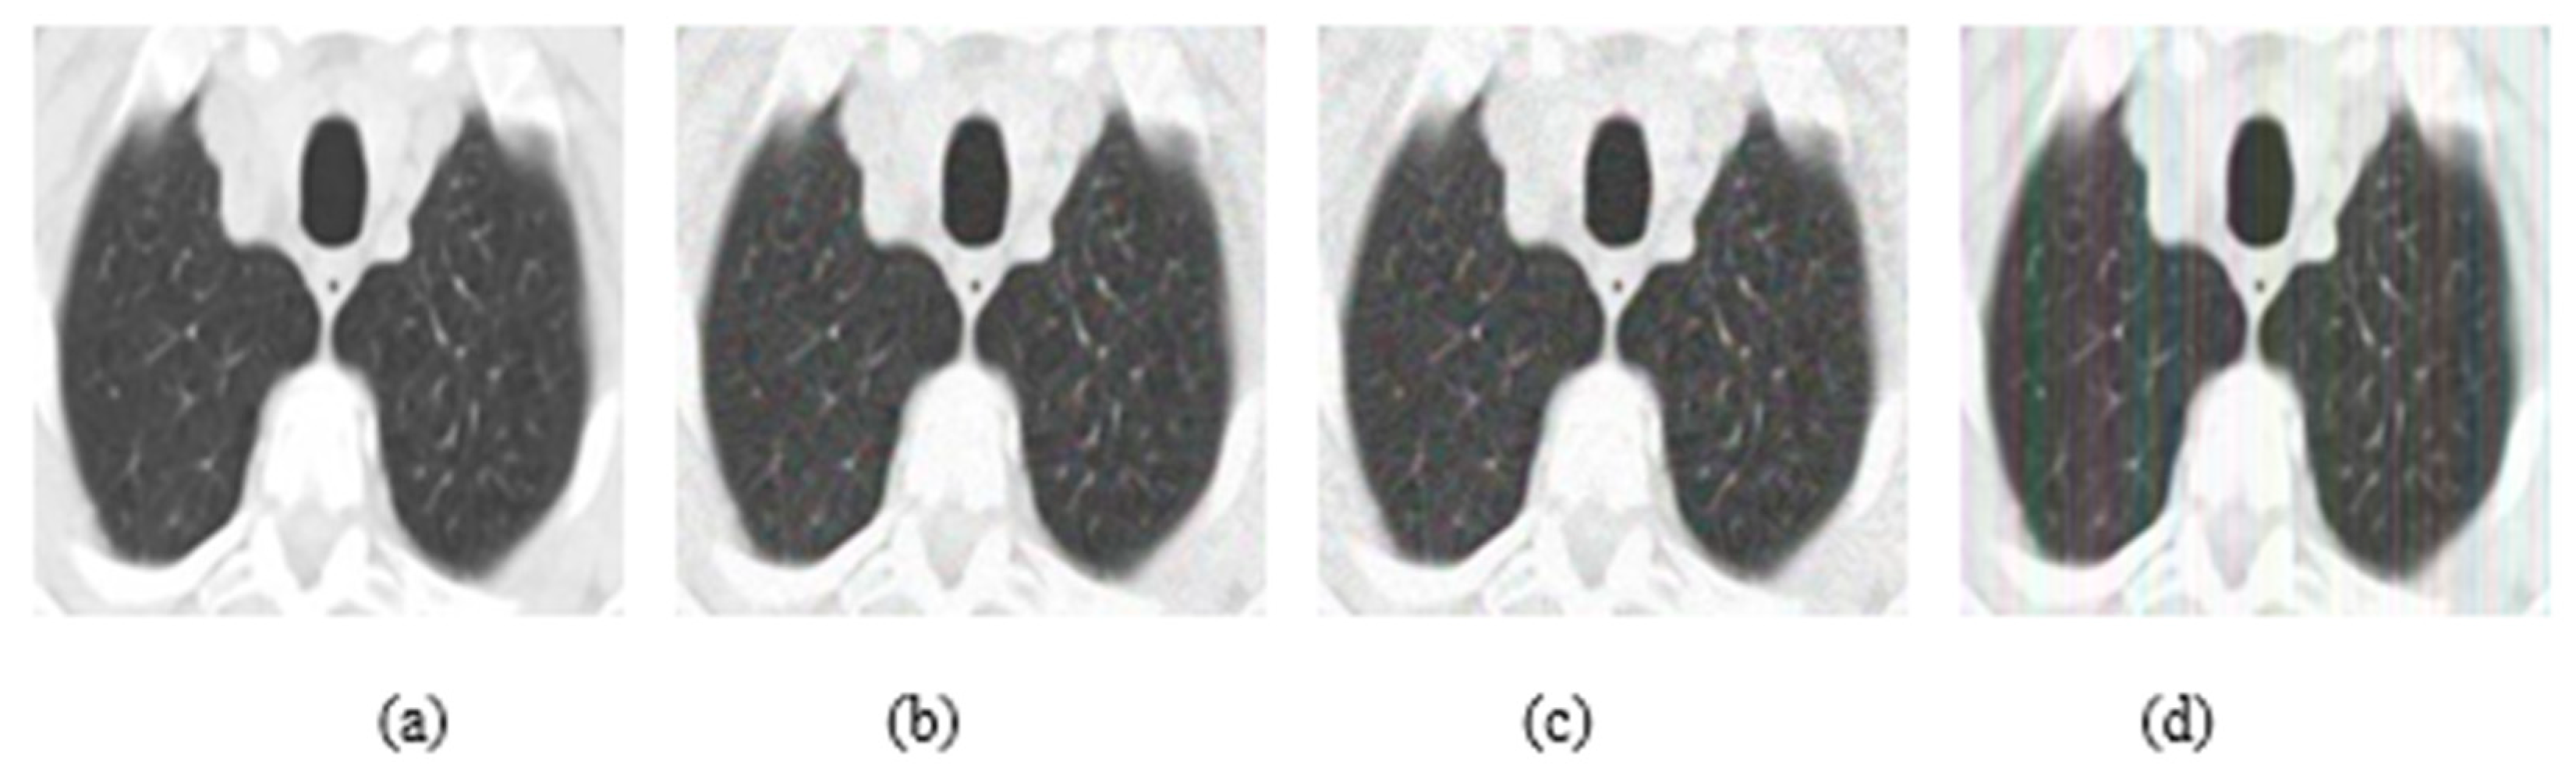

In addition, experiments were performed with FGSM, PGD, and Square Attack for ϵ values equal to 0.01, 0.03, 0.05, 0.07, 0.09, 0.12, and 0.15. In Figure 6, MRI with aforementioned attacks and ϵ = 0.01 are presented. The human eye cannot understand any difference between these images. In Figure 7, attacks with ϵ = 0.07 are depicted. Square Attack causes the biggest distortion compared to FGSM and PGD. However, small changes can be observed also in the other two attacks. In Figure 8, the ϵ value has been increased to 0.15, making the noise perceptible.

Figure 6.

(a) Initial Image, (b) FGSM attack with ϵ = 0.01, (c) PGD attack with ϵ = 0.01, (d) Square Attack with ϵ = 0.01.

Figure 7.

(a) Initial Image, (b) FGSM attack with ϵ = 0.07, (c) PGD attack with ϵ = 0.07, (d) Square Attack with ϵ = 0.07.

Figure 8.

(a) Initial Image, (b) FGSM attack with ϵ = 0.15, (c) PGD attack with ϵ = 0.15, (d) Square Attack with ϵ = 0.15.